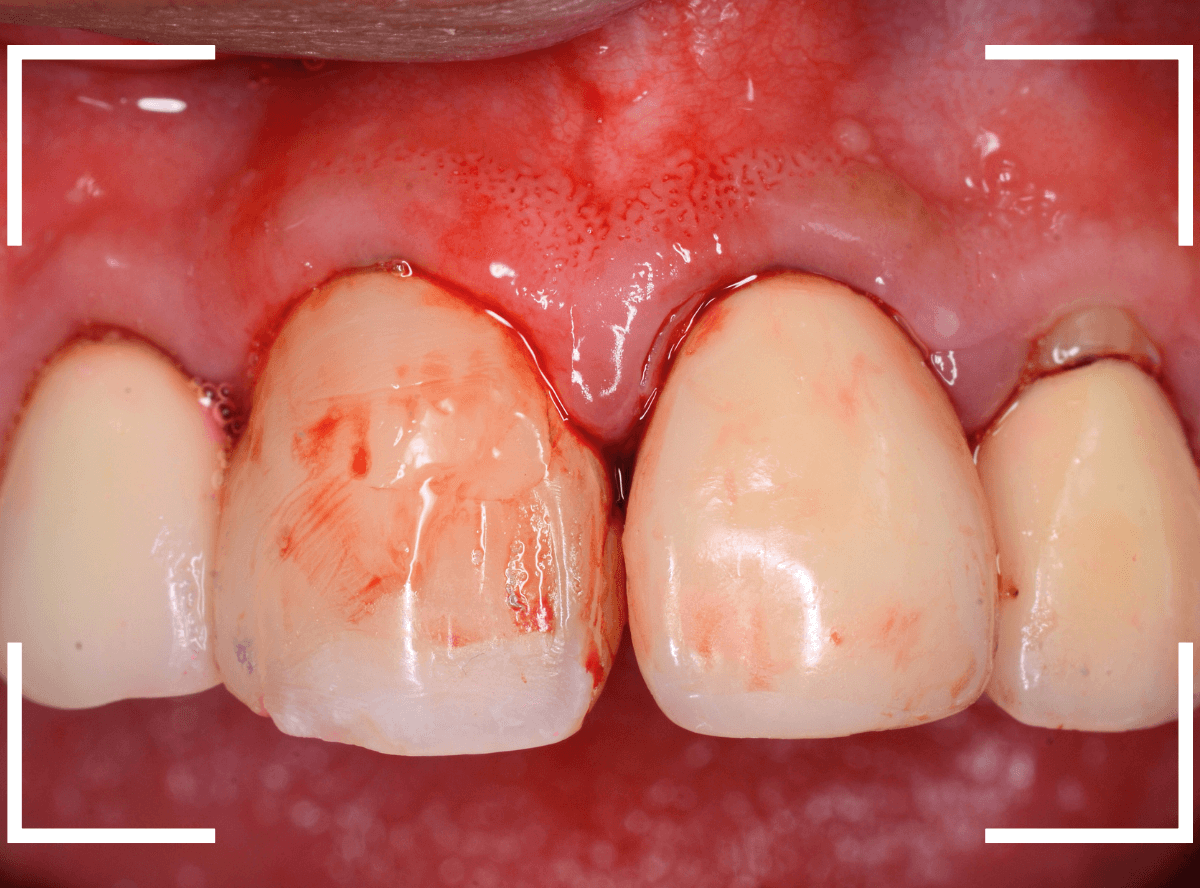

しかし、さし歯の周りを軽く歯石除去をすると、たちどころに血まみれになってしまいます。

いったい何故でしょうか?

レントゲン写真で確認します。

隣のさし歯も、ですが、さし歯の縁が見えないところで不適合になっています。

これでは、いくら歯ブラシを頑張っても、汚れがたまってしまい、歯肉の改善ができません。

歯肉にぴったりあったさし歯に作り直す必要があります。

患者さんに状況を説明して、さし歯を外して確認します。

さし歯の中は、虫歯も進行しており、想像以上にひどい状況になっているのがわかります。

この状況では、いくら歯ブラシをしてもすぐにすき間に汚れがたまってしまうでしょう。

土台(メタル・コア)も外しつつ、虫歯を除去します。

赤く染色されている部分は虫歯です。

土台の中も虫歯になっていました。

早い段階で治療が出来てよかったです。

そして、後ろの歯との境の〇部には汚れや歯石が多くつまっています。

虫歯と共に、歯の周りの縁下歯石除去も行いました。

歯の周りがきれいになっているのがわかると思います。